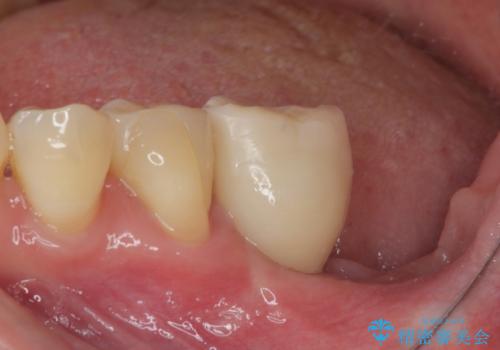

ブリッジから膿が出る 奥歯のインプラント治療

上顎は最後臼歯が欠損しているため、ブリッジの土台は抜歯し、元々の欠損部にインプラントによる補綴治療を行うこととしました。

支台歯の骨欠損は予想以上に大きく、即時荷重インプラント部への影響が心配されましたが、無事に最短期間で治療を終えることができました。